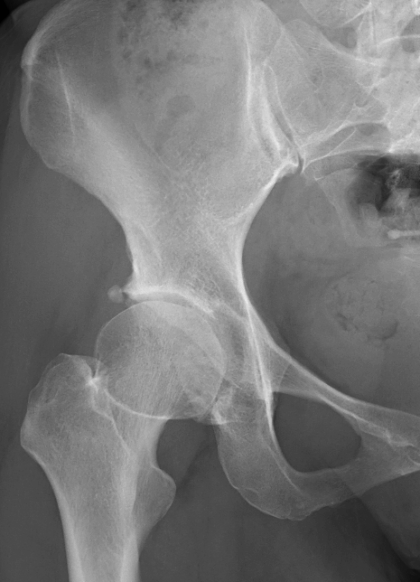

画像検査

X線(レントゲン)検査が基本となり、関節軟骨の厚みの減少(関節の隙間の狭小化)、骨棘(こつきょく:骨のトゲ)、骨嚢胞(こつのうほう:骨の中にできる空洞)の形成などを確認します 。必要に応じて、MRI検査で軟骨や周囲の軟部組織の状態をより詳細に評価します 。血液検査は、他の炎症性疾患との鑑別のために行われることがあります。

病期分類

X線所見に基づき、病気の進行度を前期、初期、進行期、末期のように分類し、それぞれの段階に応じた治療方針を決定します。